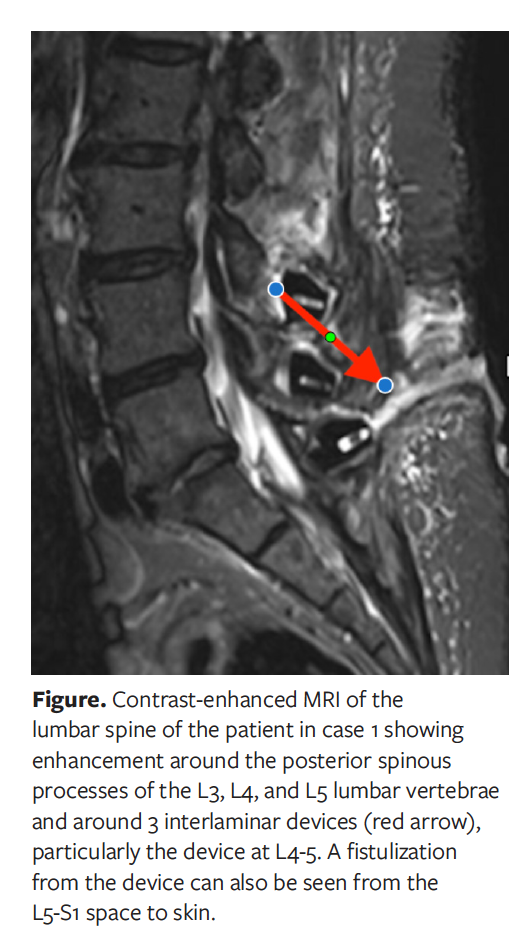

On readmission 11 months after the initial surgery, the patient presented with a non-oozing, granuloma-like skin lesion that had appeared 2 weeks earlier at the lower part of the scar. The referring physician had advised the patient to apply silver nitrate solution to the skin, but doing so resulted in no improvement. The patient had no signs or symptoms. Contamination-free removal of the skin lesion was performed at the readmission visit. The result of microbiological culture was negative. The CRP level was 3 mg/L, procalcitonin level was less than 0.2 ng/L, and WBC count was 6.400/µL. Contrast-enhanced lumbar spine MRI demonstrated enhancement around the posterior spinous processes of L3, L4, and L5 lumbar vertebrae and around 3 interlaminar devices, particularly the device at the level of L4-5, as well as a fistulization of the device from the L5-S1 space to the skin (Figure).

MRI with gadolinium contrast is the best method for detecting postoperative spine infection. MRI findings associated with infection include fluid collections with rim enhancement and ascending epidural collections.24,25 The 2 cases discussed in the current report exhibited no clinical or paraclinical findings of infection. Fistulization between the skin and device was clearly shown on MRI. The granuloma-like skin lesions in these 2 cases were suggestive of fistulization such as can occur after abdominal surgery.